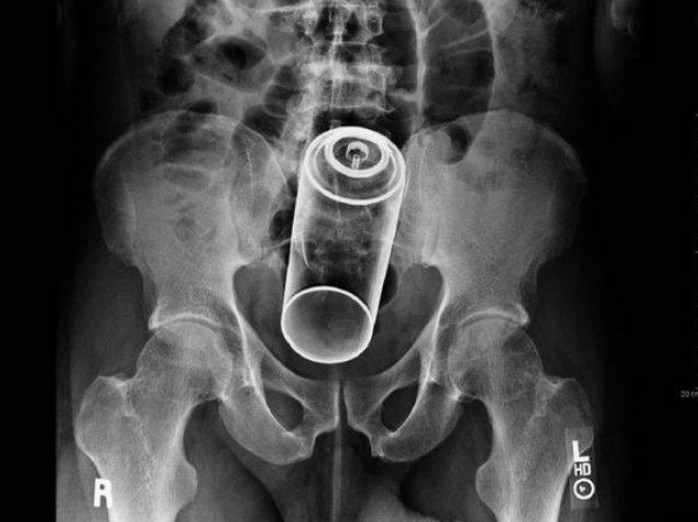

Flaschen nein, aus Glas sowieso nicht,  aber probiert mal Getränke- und Spraydosen. Und die zuvor im Kühlschrank gelagert, das ist der Wahn! Siehe meine Bilder. :-)

Auch DAS kann richtig in's Auge ........ oder in den Anus gehen...dose.jpg

Auch Getränke oder Spraydose kriegt man zum Teil nicht mehr raus! Besonders "lustig" ist wenn von der Spraydose der Deckel abspringt und dann mit der recht scharfkantigen Öffnung nach unten im Enddarm hängt.

Immer was nehmen was man an Kette, Band etc selbst wieder rauskriegen kann!!